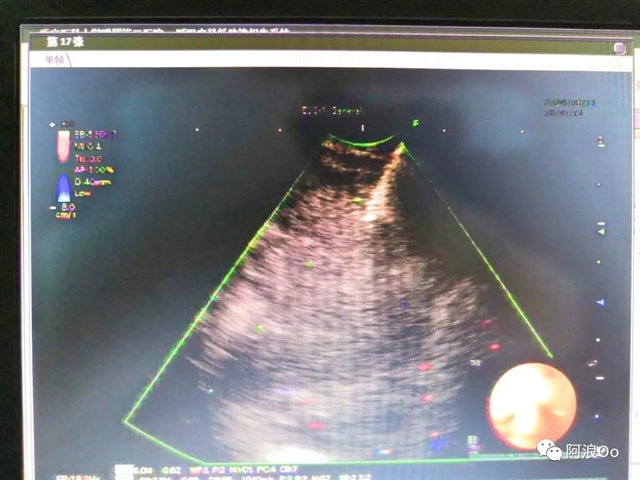

国内首位!李长毅开展电刀辅助下经气管纵隔活检钳取活检技术(Cautery Assist Transbronchial For cep Biopsy,Ca-TBFB):超声支气管镜引导,经过气管软骨环用针形电刀切开气管粘膜进入纵隔,以活检钳进行纵隔钳取活检。相对于传统TBNA和eBUS-TBNA,能够取得大块组织标本,对于纵隔良性疾病、淋巴瘤具有明显优势。淋巴结坏死明显,多次eBUS-TBNA拿不到病理依据,可以作为备选技术。